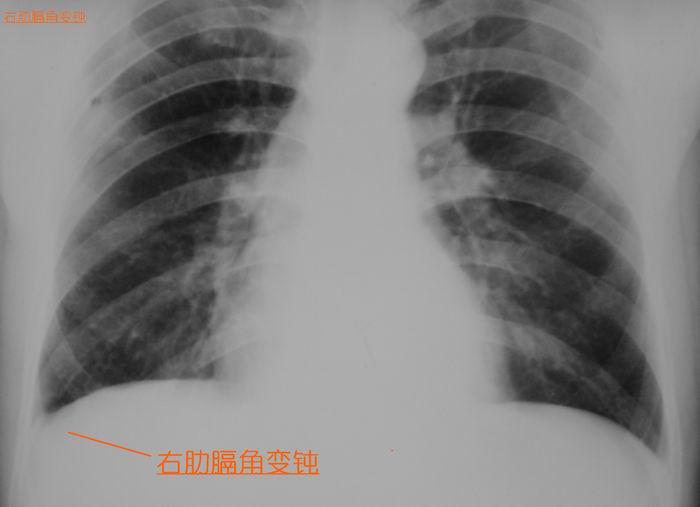

伤者今天上午又来照了胸正斜位、立腹片、腰椎片:

应该是与外伤有关的影像表现。血肿不太象!会不会是创伤性膈疝

后纵隔血肿,右胸腔少量积液,建议排除外伤外其它病变

血肿不太象!会不会是创伤性膈疝?